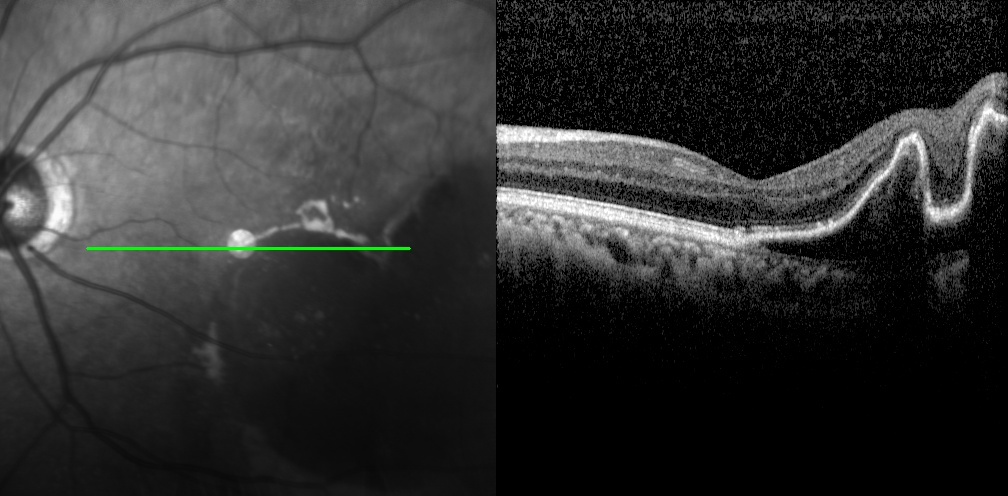

老王左眼檢查圖片

左眼調(diào)整用藥半個(gè)月后檢查圖片